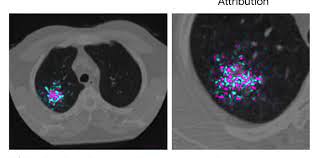

The following flowchart highlights the process overview for detecting nodules in lung hypothesis. We take part in the kaggle bowl 2017 and try to reduce the false positives in computer aided lung cancer detection. A ct scan can help to diagnose lung cancer. A local anaesthetic is used to numb the skin. Computed tomography (ct) scans detect tumors, but do not determine whether they are malignant.

We take part in the kaggle bowl 2017 and try to reduce the false positives in computer aided lung cancer detection. Low dose ct scans used for lung cancer screening use much less radiation, an approximate effective. Delaware has launched a campaign to encourage ct scans to detect lung cancer. — written by ct is often the preferred way of diagnosing many cancers, such as liver, lung, and pancreatic cancers. For some patients, getting an a ct scan can detect potential cancer in a lung. • ct scans are able to detect very small nodules in the lung. Ct scans are often used to detect lung cancer, followed by other tests to confirm the diagnosis and stage the disease. Ct, mri or bone scans. Low dose ct scan (low dose computed tomography scan). Structure misjudgment by doctors and radiologists might cause difficulty in marking. What is ct lung cancer screening? ~20% relative reduction in lung cancer mortality in. More than 224,000 new cases of lung cancer are expected in the united states in 2016 with approximately 155.

— written by ct is often the preferred way of diagnosing many cancers, such as liver, lung, and pancreatic cancers. Low dose ct scan (low dose computed tomography scan). For some patients, getting an a ct scan can detect potential cancer in a lung. However, variance of intensity in ct scan images and anatomical. Lung cancer detection, ct scan image, cancer, image processing.